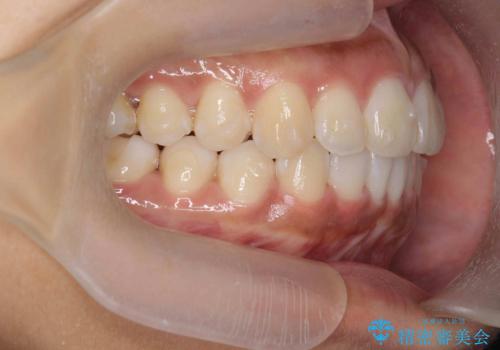

出っ歯感のある前歯を治したい、抜歯をしないマウスピース矯正

- 前歯のガタつき、突出感のある前歯の改善を求めて来院されました。

前歯の角度を改善し審美性を高めるとともに、奥歯のガタつきも並べ直すことで安定した咬合関係の確立を目指します。

歯列の側方拡大をしっかりと行ったことで歯を抜かずに前歯の角度をしっかりと改善することができました。